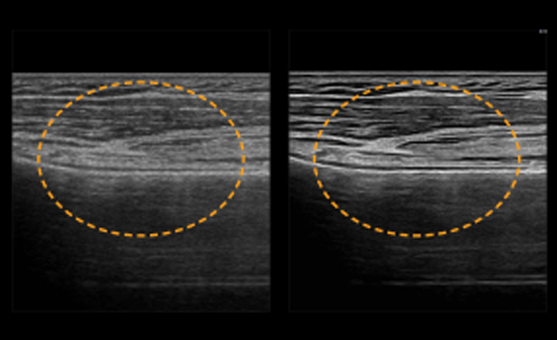

ShadowHDR aplică în mod selectiv ultrasunetele de înaltă sau joasă frecvență pentru a identifica zonele întunecate, cum ar fi capul sau coloana vertebrală a fătului, unde verifică atenuarea și compensează acestea permițând o mai mare vizibilitate a țesăturii.

HQ-Vision oferă imagini mai clare prin atenuarea zonelor de imagine care sunt mai neclare decât natura lor reală

Filtrul de reducere a zgomotului îmbunătățește definiția marginilor și creează imagini 2D clare pentru performanțe optime de diagnosticare. În plus, ClearVision oferă optimizare specifică aplicației și rezoluție temporală avansată în modul de scanare în timp real.